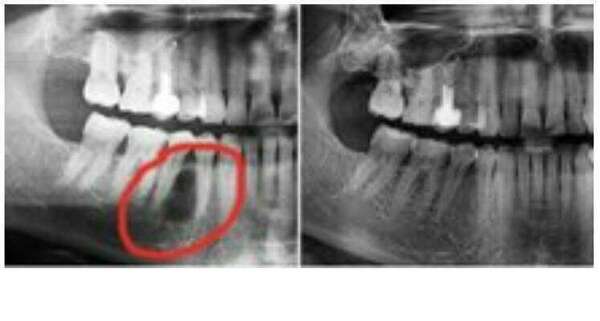

Le soin, désinfection , obturation des racines,

* lorsque la vitalité de la dent n'a pu être sauvegardée.

* la reprise de ce traitement des racines quand il y a des complications infectieuses sur les racines, Kystes ou granulomes.